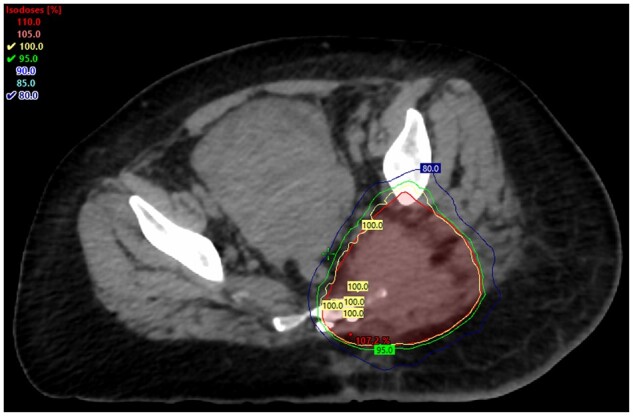

Classic Hodgkin lymphoma is a potentially curable disease. With the advent of effective systemic regimens with adriamycin, bleomycin, vincristine, and dacarbazine, chemotherapy has become the treatment of choice for advanced Hodgkin lymphoma. However, for advanced Hodgkin lymphoma after chemotherapy, disease relapse rates are still high. This case report highlights how low-dose palliative radiotherapy can be used successfully for the management of an unusual case of recurrent lymphoma with a different histology soon after completing systemic therapy, which was further complicated by an ongoing local infection.